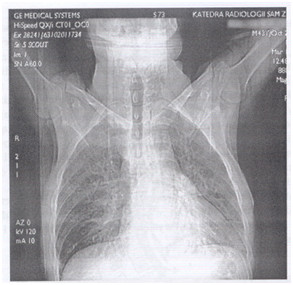

U chorego, lat 33, bez dolegliwości, w dobrym stanie ogólnym wykonano rutynowo rtg klatki piersiowej (przed rozpoczęciem nowej pracy), a następnie KT (obraz poniżej). Jakie jest najbardziej właściwe dalsze postępowanie?